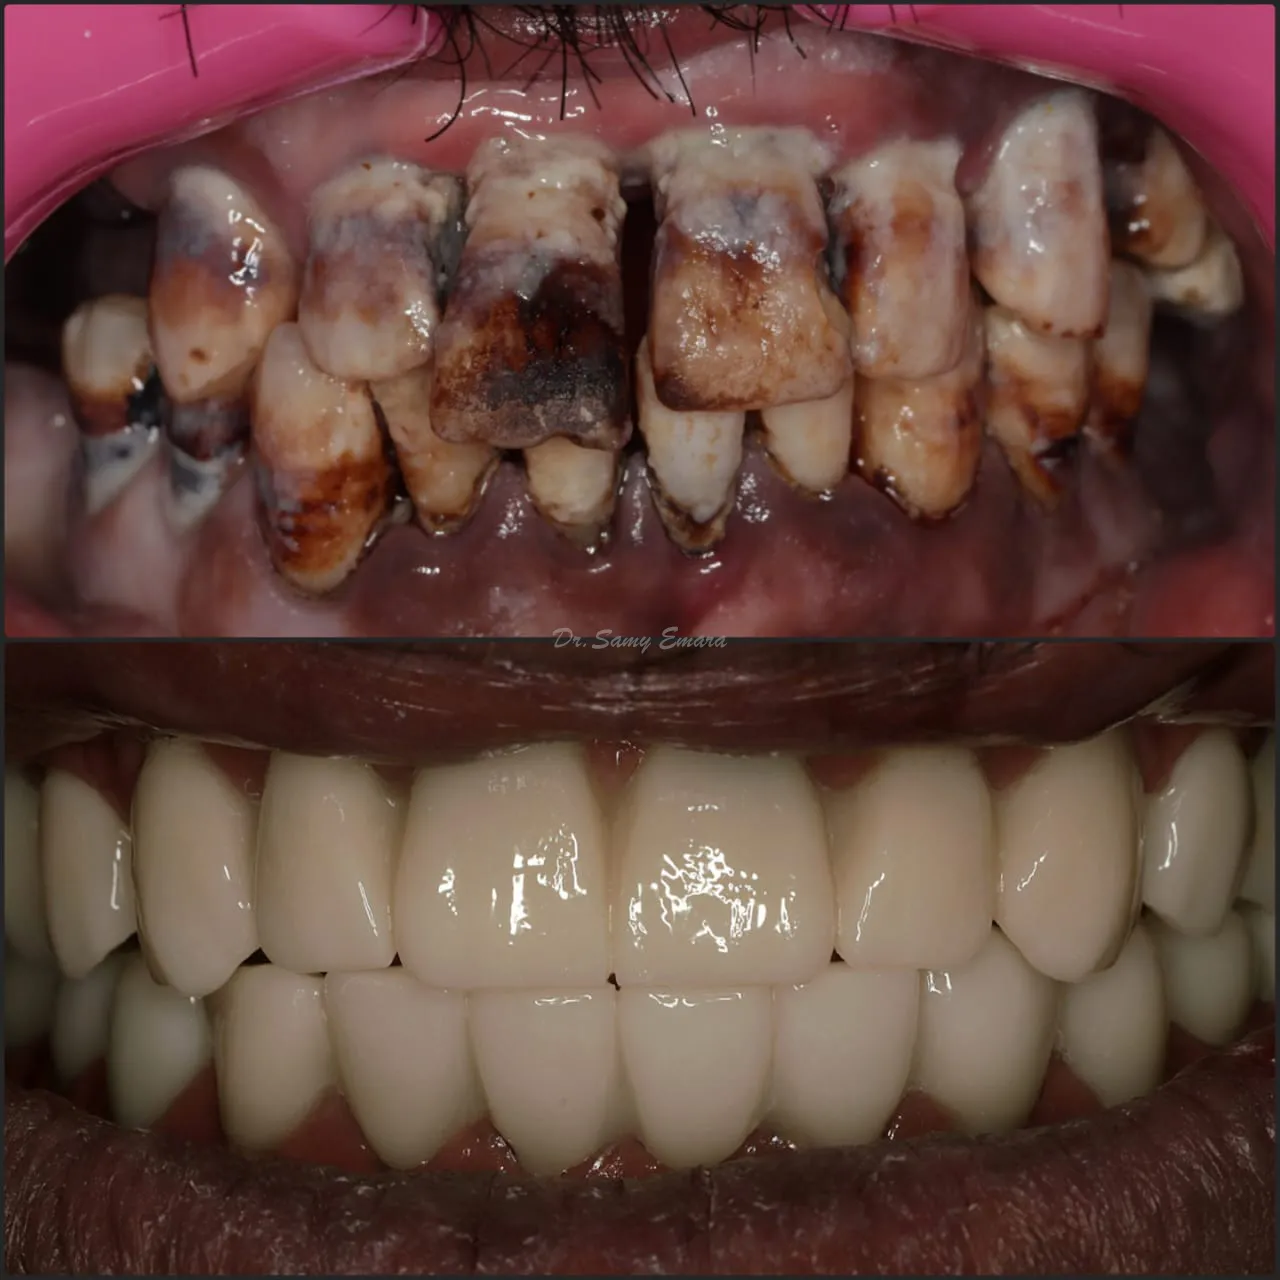

Full Mouth Reconstruction